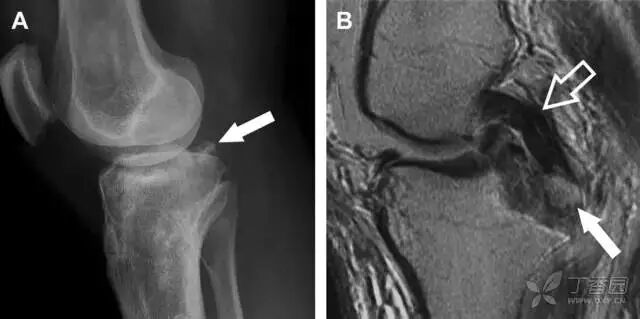

12反向 Segond 骨折

胫骨平台内侧皮质骨撕脱性骨折,被称为内侧 Segond 骨折或反向 Segond 骨折(图 5)。这种骨折的旋转机制与 Segond 骨折相反,该骨折与后交叉韧带断裂及内侧半月板损伤相关。

图 5 一位足球运动员的反向 Segond 骨折

A 正位片示关节线处的胫骨内侧见一细小骨折片(箭头)。B MRI 冠状位 T1 加权像示骨折片出现在内侧副韧带关节囊附着处(方框)。